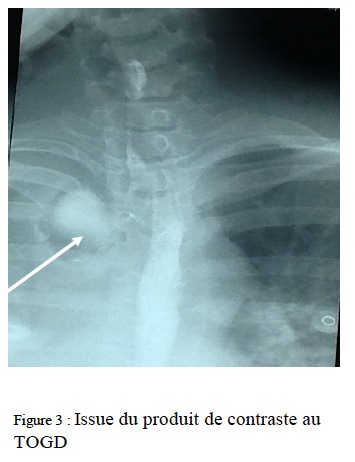

Un transit à la gastrografine avait montré un pertuis oesophagien avec fuite du produit de contraste (figure 3),